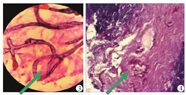

例3 与例2为同一供肾来源,术后受者出现DGF,予以ATG抗排斥反应治疗5 d;术后第8天开始出现咳嗽,咯咖啡色浓痰,痰培养显示涂片丝状真菌(+),生长毛霉菌;术后第9天首次行纤维支气管镜检查显示右中下肺支气管内见大量灰白色物质覆盖(图2),肺泡灌洗液培养涂片提示毛霉菌感染(图3),纤维支气管镜下组织活检病理报告诊断:"右中间支气管"支气管黏膜慢性炎并毛霉菌菌落(图4),加用两性霉素B脂质体(逐日递增至维持剂量1 mg·kg-1·d-1)抗真菌治疗;术后第35天复查纤维支气管镜检查显示,右主支气管及右中下叶支气管见灰白色异生物堵塞(图5),遂在纤维支气管镜下行氮气刀治疗半小时,并加服泊沙康唑(20 ml/d)抗真菌治疗;术后第42天纤维支气管镜下第2次行氮气刀治疗,较第一次氮气刀治疗相比堵塞处有所通畅。经过二次氮气刀治疗后术后第49天复查纤维支气管镜检查提示,原堵塞处未见明显异生物,较前明显通畅;术后53 d受者经纤维支气管镜亚氮刀治疗后病灶基本吸收,出院。出院后受者继续口服泊沙康唑抗真菌治疗,MMF从0.5 mg/d逐渐加量恢复至正常剂量。整个治疗过程中,他克莫司均按正常剂量1/3口服,血他克莫司浓度控制于5~8 μg/L,两性霉素B脂质体共使用32 d,泊沙康唑共使用90 d,治疗期间尿量基本正常,血肌酐波动于98~157 mmol/L,未发生排斥反应。